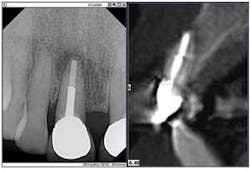

Here's where the second part of the duo, my CBCT system, came to my rescue. The 3-D image provided the further evidence of a horizontal root fracture.

Furthermore, the radiolucency extended both mesially and distally, and the lesion had invaded the facial plate, necessitating a more extensive surgery — good to know before making the incision. The 3-D scan presented me with a clear image of the extent of the bone destruction, the need for a bone graft, and the possible additional need for a membrane.